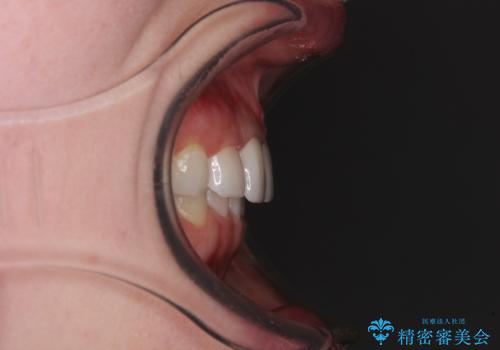

- 前歯の歯並びと虫歯を気にして来院された患者様です。

上下前歯の歯列不正はインビザラインにより歯列を整え、その後に、前歯5本をオールセラミッククラウンにて補綴治療することとしました。

矯正治療前に前歯のむし歯治療を行ったものの、樹脂で充填するには虫歯が広範囲であったため、審美的に問題がありました。